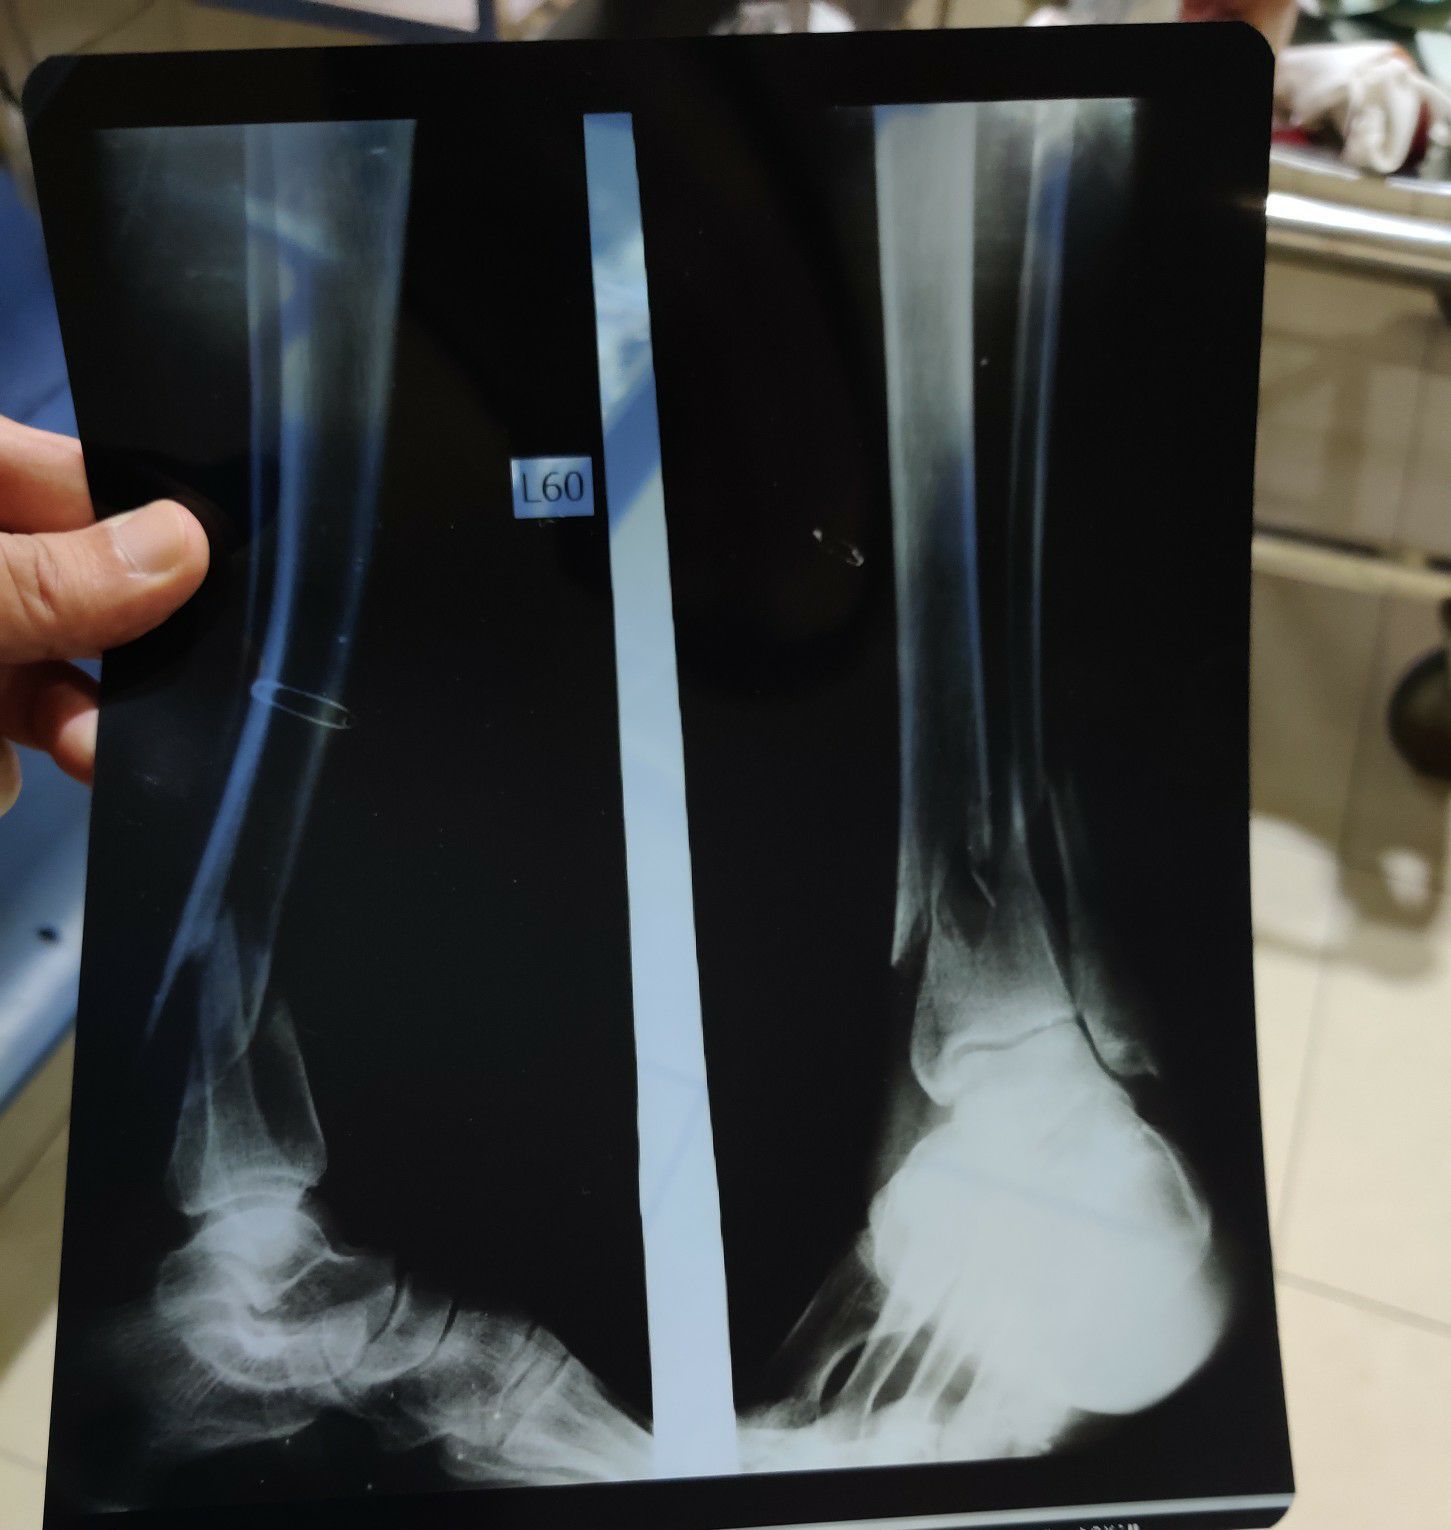

Tibia/Fibula Fracture

Tibia

Fibula